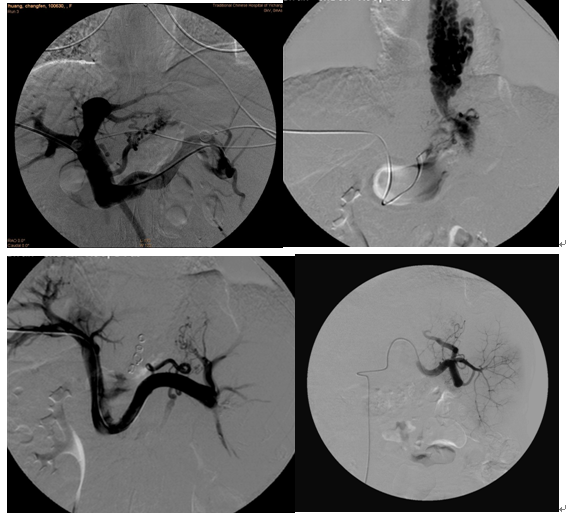

典型病例:女、46岁,肝硬化门静脉高压反复出血,在我院DSA引导下行经皮穿刺食管胃底静脉曲张栓塞术+部分性癖栓塞术后至今未再发生出血。